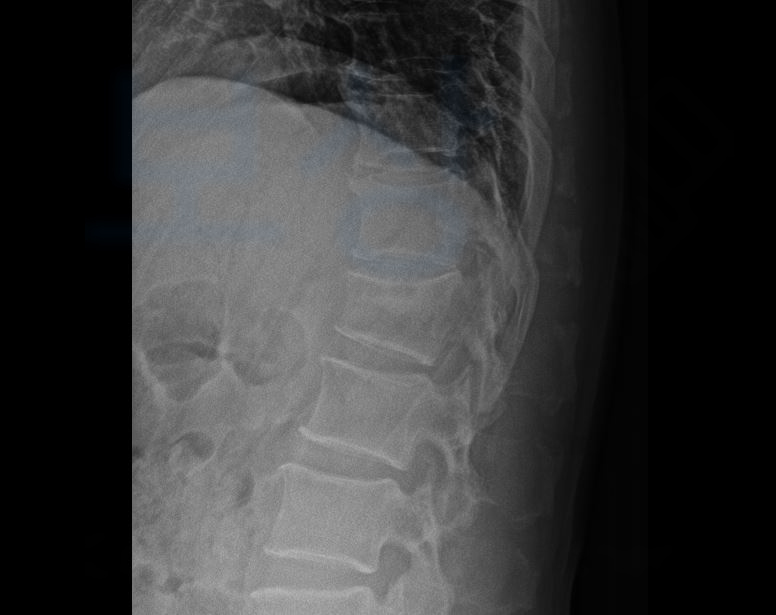

안녕하세요. 보상파트너입니다. 요추1번 부위는 흉추의 후만과 요추의 전만이 교차하는 부위이이기 때문에 교통사고, 추락사고, 낙상사고에 의해 요추1번 척추압박골절 되는 상황이 빈번하게 발생합니다.

강하게 치고 갔기 때문에 윤@@님은 크게 넘어지셨으며 급히 응급실에 내원하여 정밀검사를 받은 결과,

L1 골절, 폐쇄성 S32020 L은 Lumbar 즉 요추의 약자로서 L 옆에 붙은 숫자는 척추체의 번호를 의미합니다. 따라서 L1 골절은 요추1번의 골절을 의미하죠. 윤@@님은 최소 6주간의 침대에서 안정을 또 일어나실 때는 척추압박골절보조기 착용하시면서 뼈가 잘 유합될 수 있도록 각별한 관리가 필요하였습니다.

요추1번 척추압박골절 진단받으면 보조기를 착용하며 수술을 안하셨더라도 골절된 척추체가 원통모양에서 찌그러지면서 척추의 각도에 기형을 야기합니다. 또한 척추체가 눌리고 찌그러져 한 척추체가 부담하는 하중도 커지는 압박률도 커지게 되죠.